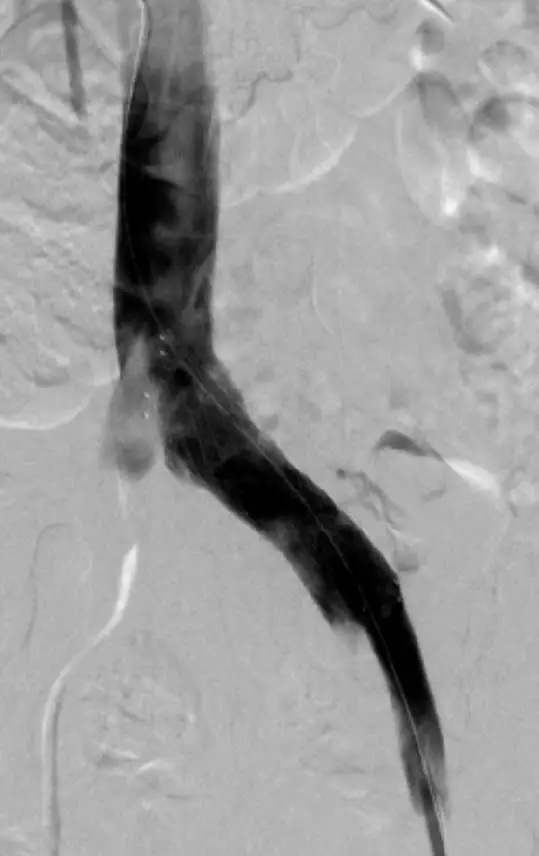

Figura 2. Venograma de sustracción digital tras implantación de un stent oblicuo de 80 mm en la vena ilíaca común izquierda.

El síndrome postrombótico (SPT) es una complicación crónica común de la trombosis venosa profunda (TVP). El 80% de los pacientes con TVP iliofemoral tienen una anomalía anatómica subyacente. La forma más común es la compresión de la vena ilíaca común izquierda por la arteria ilíaca común derecha predominante y la quinta vértebra lumbar (síndrome de May-Thurner).

El estudio monitorizado internacional TOPOS en curso incluyó a 60 pacientes con síndrome postrombótico tratados con el stent del Sinus Obliquus y la extensión con stent distal cuando se requería.

A los 12 meses de seguimiento, se obtuvieron las tasas de permeabilidad de la ecografía Doppler y los resultados clínicos se evaluaron mediante la puntuación de Villalta, la puntuación de gravedad venosa revisada (rVCSS, por sus siglas en inglés), la puntuación de intensidad del dolor y el cuestionario de calidad de vida de la enfermedad venosa crónica (CIVIQ-20, por sus siglas en inglés).

A los 12 meses, las tasas de permeabilidad primaria, primaria asistida y secundaria fueron del 90% (IC del 95%: 55,5 a 99,7%), 100% (IC del 95%: 69,2- 100%) y 100% (IC del 95%: 69,2%-100%) en pacientes con el stent obliquo autoexpandible solamente, y 81,4% (IC 95% 66,6-91,6%), 88,4% (IC 95% 74,9-96,1%) y 97,6% (IC 95% 87,4-99,9) en pacientes con extensión de stent por debajo del ligamento inguinal, respectivamente.

A los 12 meses, el 60% de los pacientes no presentaban síntomas de SPT; 18% tenía SPT leve, el 7% moderado y el 2% grave. La mejoría en Villalta, rVCSS, CIVIQ-20 y EVA desde el inicio hasta el seguimiento fue de 8,4 ± 6,9 (IC del 95%: 6,5-10,3; p <0,0001; n = 52) puntos , 5,1 ± 3,5 (IC del 95%: 4,1-6,1; p <0,0001; n = 51) puntos, 15,6 ± 12,4 (IC 95% 12,1-19,1; p <0,0001); n = 50) puntos y 2,9 ± 2,2 (IC 95% 2,3-3,5; p <0,0001); n = 50 puntos, respectivamente.